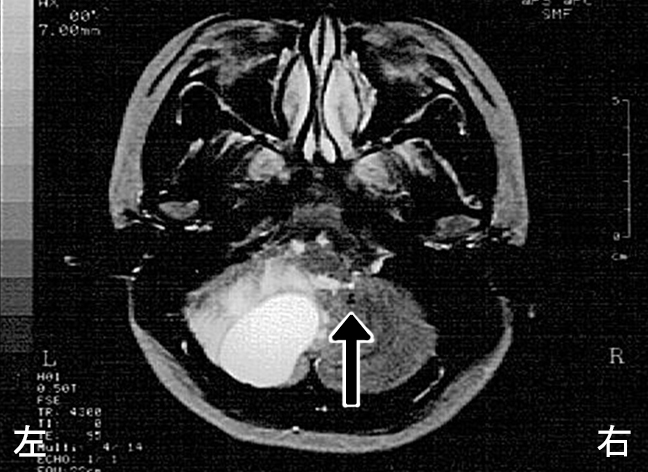

第5病日のMRIでは、第Ⅳ脳室の右方偏移・圧排された左側側脳室・大脳鎌ヘルニアなどの所見が得られた(図3・4)。

図3 MRIにて第Ⅳ脳室の圧排と、右方偏移が見られる。(プロトン強調画像)

図4 MRIにて圧排された左側側脳室①と、右方への大脳鎌ヘルニア②が観察される。(T1造影MRI)

本症例は脳神経外科受診後、生命の危険を指摘され、即日入院となった。実際CT(図2)やMRI(図3・4)では、第Ⅳ脳室の圧迫と右方偏移・圧排された左側側脳室・大脳鎌ヘルニアなどの所見が得られ、眼底所見を併せて考えると水頭症の進行から脳幹の圧迫に至る危険性も、否定できなかった。